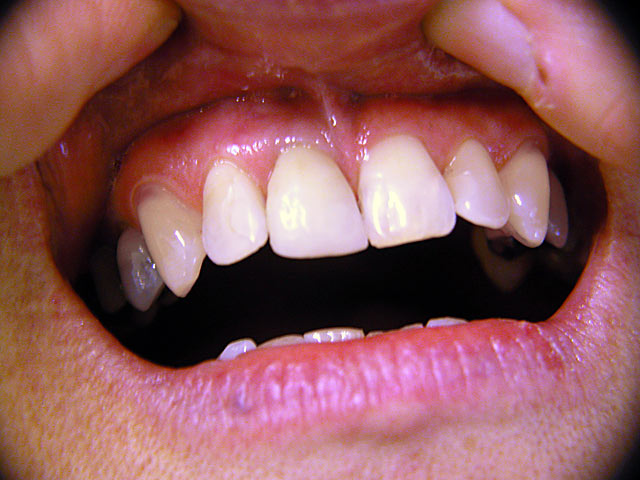

Die folgenden Patientenfälle sollen Ihnen einen Einblick in die Möglichkeiten der modernen Implantation geben.

Frontzahn-Implantation:

Implantation – Patientenbeispiel 1: